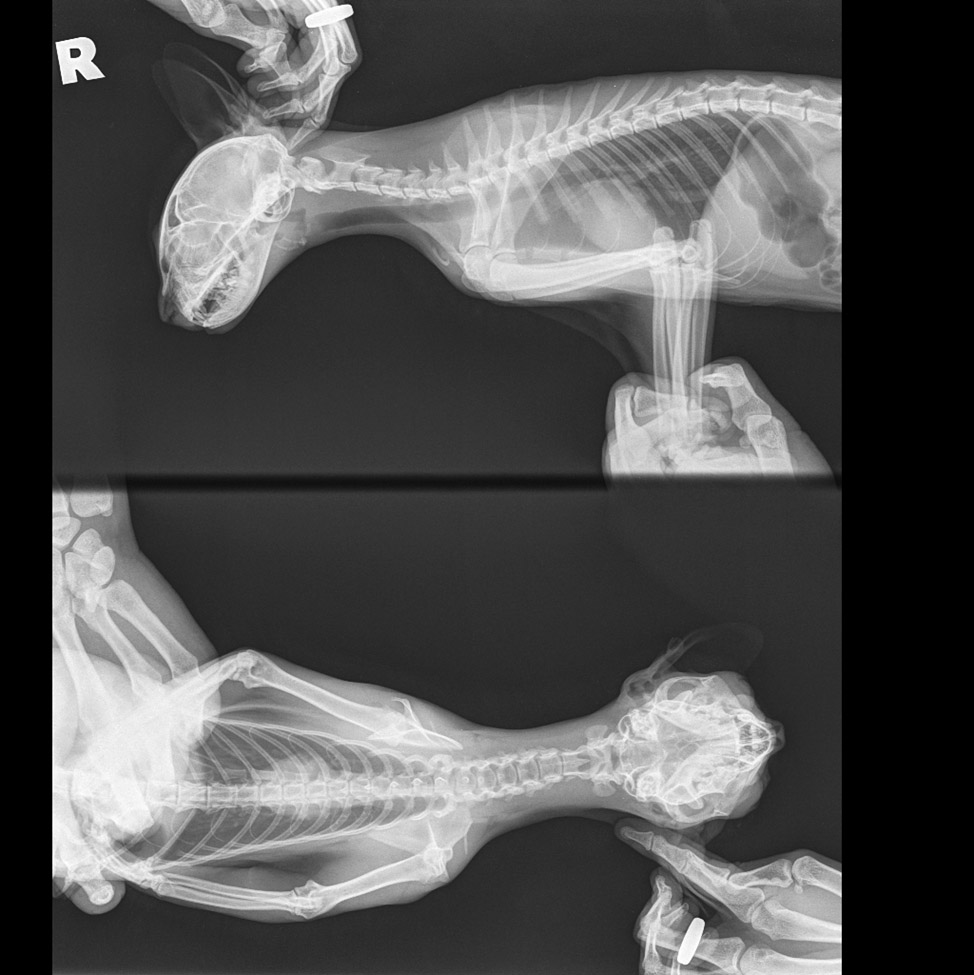

Рентгеновские снимки анатомии собак: строение и здоровье